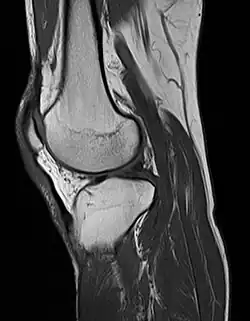

MRI uses strong magnetic fields to align atomic nuclei (usually hydrogen protons) within body tissues, then uses a radio signal to disturb the axis of rotation of these nuclei and observes the radio frequency signal generated as the nuclei return to their baseline states.[15] The radio signals are collected by small antennae, called coils, placed near the area of interest. An advantage of MRI is its ability to produce images in axial, coronal, sagittal and multiple oblique planes with equal ease. MRI scans give the best soft tissue contrast of all the imaging modalities. With advances in scanning speed and spatial resolution, and improvements in computer 3D algorithms and hardware, MRI has become an important tool in musculoskeletal radiology and neuroradiology.

One disadvantage is the patient has to hold still for long periods of time in a noisy, cramped space while the imaging is performed. Claustrophobia (fear of closed spaces) severe enough to terminate the MRI exam is reported in up to 5% of patients. Recent improvements in magnet design including stronger magnetic fields (3 teslas), shortening exam times, wider, shorter magnet bores and more open magnet designs, have brought some relief for claustrophobic patients. However, for magnets with equivalent field strengths, there is often a trade-off between image quality and open design. MRI has great benefit in imaging the brain, spine, and musculoskeletal system. The use of MRI is currently contraindicated for patients with pacemakers, cochlear implants, some indwelling medication pumps, certain types of cerebral aneurysm clips, metal fragments in the eyes, some metallic hardware due to the powerful magnetic fields, and strong fluctuating radio signals to which the body is exposed. Areas of potential advancement include functional imaging, cardiovascular MRI, and MRI-guided therapy.